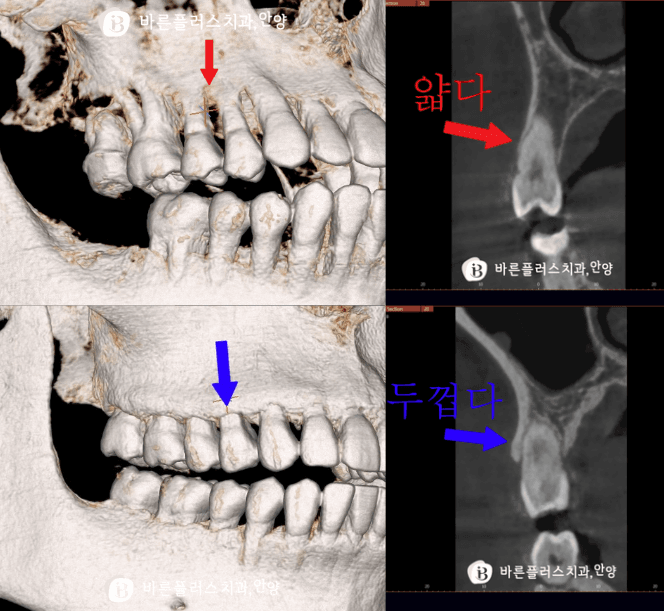

위사진 상 하 케이스를 보시면 동일 성별, 비슷한 연령대이며, 구강 관리도 비교적 잘 되어 있음에도 치아를 덮고있는 잇몸높이가 차이가있음을 보입니다. 원인1. 타고난 잇몸과 치아의 형태 사람마다 잇몸의 두께는 타고납니다. 잇몸이 얇은 타입(thin type)은 외부 자극에 상대적으로 취약해 강한 양치 습관이 반복되면 잇몸이 벗겨짐(잇몸퇴축) 쉽게 발생합니다.

원인2️. 치조골의 두께 A 잇몸을 가진 분의 3D CT상에서 뼈의 두께를 확인시, 뼈가 얇은것을 볼수가있습니다. 반면 B잇몸을 가진분의 3D CT상에서 뼈의 두께는 상대적으로 두꺼운것을 볼수가있습니다.

좀더 자세한 3D단면에서 뼈의 두께 차이가 잇몸 벗겨짐과 관련성이 있음을 확인할 수 있습니다.